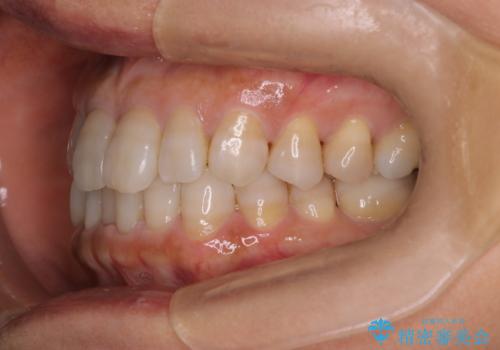

【インビザライン】下前歯だけを治したい

- 50代女性

- 矯正装置

- インビザライン

- 治療期間

- 8ヶ月

- 下前歯のがたつきにより唇を巻き込んでかんでしまい痛いため矯正をしたいという主訴で来院されました。今回は下顎前歯のみという強い希望があり、下顎のみのインビザライン矯正をしました。

叢生を改善するためのスペースはIPRと拡大を行いました。治療後は唇を巻き込んでしまう主訴が改善し、ご満足していただけました。